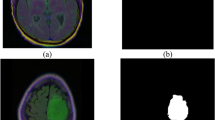

A performance comparison has been done with the recent work done by34 and other state-of-the-art techniques29,35,36,37,38,39,40 in image segmentation that employ deep learning models as portrayed in Table 1. A detailed ablation study of the proposed model is presented in Table 2, where the effect of introducing each component of the model can be seen in the final results. The segmentation network’s segmented output image, in contrast with the source MRI image and the ground truth, is illustrated in Table 3.

To analyze the efficiency of the proposed model, it is also tested on BraTS2019 dataset. The visual comparison analysis is shown in Table 5. It illustrates the segmentation network’s segmented output image, in contrast with the source MRI image and the ground truth. Table 2 presents a detailed ablation study of each component of the proposed model. It can be seen from column (ii) that the introduction of the custom LCFT loss function replacing the typical Dice loss showed great improvement in all three segmentation-specific metrics. From Tables 3 and 5, it is observed that the custom LCFT loss function had the most significant impact on the performance of the proposed model. This is because it helps in reducing the overall false positives and false negatives in the segmented image.

A few test images from each of the five conditions are shown in Table 3, for a side-by-side comparison of the predicted image of the model and the actual ground truth. Even though the proposed model achieves excellent results, it is a limitation that a high-end GPU with a significant amount of memory and computation power is essential to train the model. Another drawback is that the batch size had to be reduced in order to carry out the training process with limited RAM, which may have introduced a generalization gap. This had to be overcome by other methods, like introducing dropouts and other generalization techniques. The overall parameters required for the 5 stages are 280.52 MB whereas the 4 stages model requires only 73.61 MB. The total inference time for the five stage network is 6534. 740 s whereas for proposed four stage model takes only 4230.856 s to train the model completely.